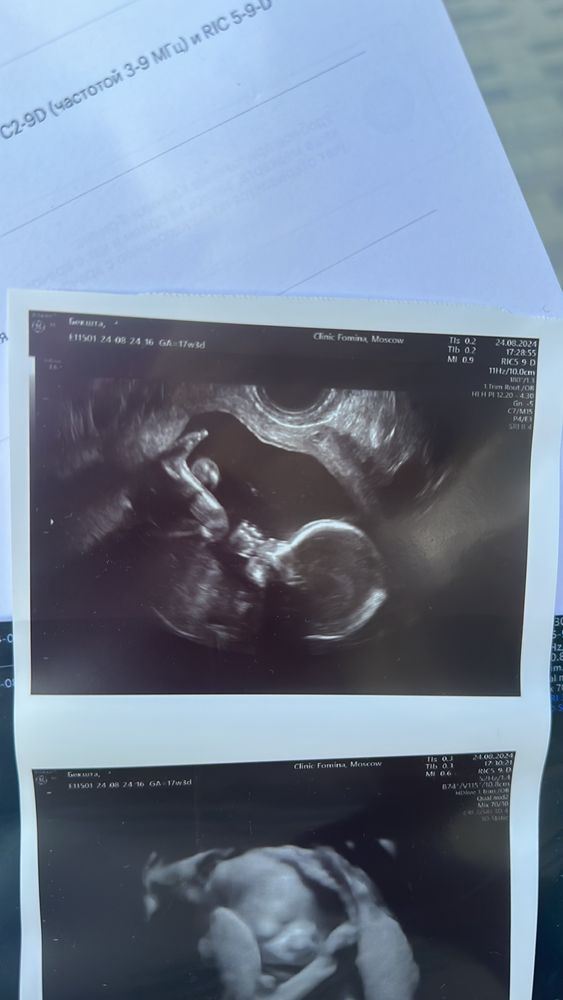

а так малая развивается в срок, все у нее прекрасно, надеюсь мой организм ее доносит до 36-38 недели хоть..и не сдастся раньше времени)

на всякий случай есть плазмоферез для очищения крови. Главное чтобы с ней все было хорошо и вот наши фото)